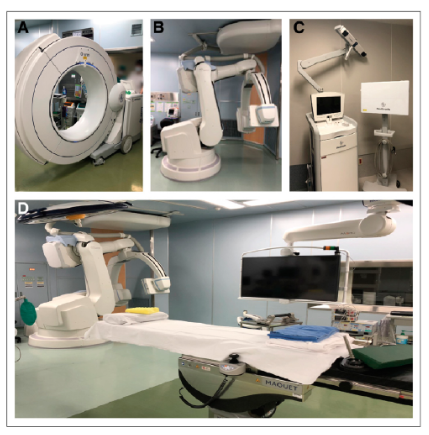

【先進機器の導入】

従来の手術では医師の経験によって手術成績にばらつきがあるという問題がありましたが、当院ではO-arm 2やロボットCアームなどの最先端の手術支援機器を導入することで、安全性の向上に注力しています。これに加えて、通常のナビゲーションに加えて術中3D画像撮影が可能な機器も活用しています。

また近年では3D可視化技術の応用にも力を入れており、AR、MRを用いた更なる低侵襲で安全な手術治療への取り組みも始まっています。

また、頚椎症性脊髄症や側弯症などの疾患に対しては、最新の設備を駆使して手術を行っています。具体的には、CTナビゲーションや脊髄刺激モニタリング、自己回収輸血などを利用して、安全性に配慮した手術を実施しています。また、新しいインプラントの導入により、人間の本来の弯曲に近い矯正術が可能となっています。

肩甲骨烏口突起骨折に対しては当院で導入しているO-arm navigation systemを使用しての骨折治療を行っております。